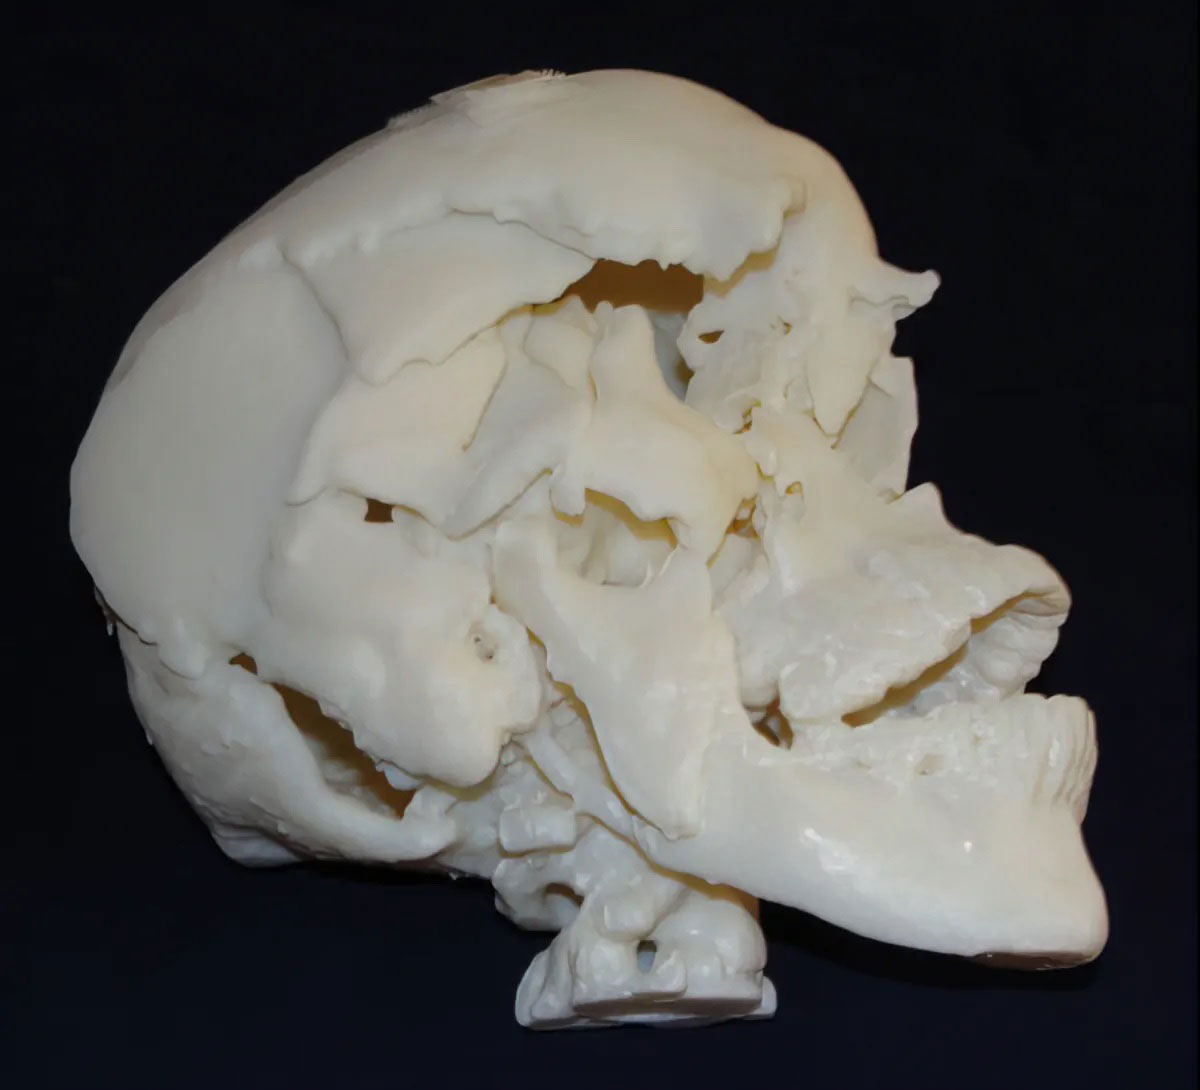

Those not trained in the medical field may not easily understand the data presented in medical imaging. A postmortem scan shows numerous fractures in the skull of a 60-year-old man who was stomped to death by his son. The use of 3D printing helped provide a clear visual representation of the complex medical imagery and the jury’s understanding.